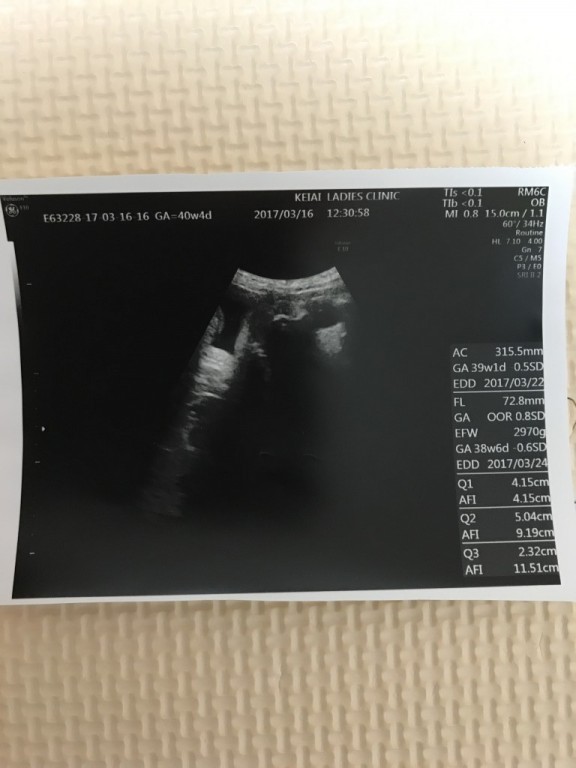

妊娠10ヶ月(36週0日)撮影日:2018年3月16日

なおはる